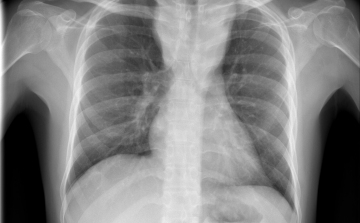

Egy líbiai menekülttáborból érkezhetett Európába a tbc egy új kórokozója

Menekültek révén, egy líbiai táborból érkezhetett Európába a tuberkulózis (tbc) kórokozójának egy korábban ismeretlen, gyógyszerekkel szemben ellenálló fajtája - írta a Die Welt című német lap a hírportálján szerdán.

Csökkent a tbc-fertőzések száma Európában

Átlagosan 4,3 százalékkal csökkent az új tuberkulózisos (tbc-s) esetek száma 2010 és 2014 között az Egészségügyi Világszervezet (WHO) 53 országot magába foglaló európai régiójában.